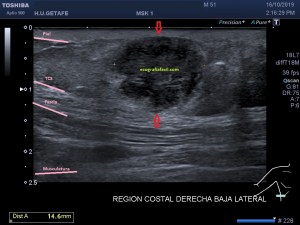

En la imagen 3 ves una imagen de un lipoma, mide 7 cms, la huella de la sonda mide 5cms, la «panoramic view» posee una regla centimetrada que sigue el contorno de la imagen, justo en la profundidad de la misma y lo marca la flecha amarilla. La profundidad la marca la flecha roja y la flecha blanca marca el rango centimetral de los 5cms, fíjate que la línea blanca es ligeramente mayor cada 5 cms. Sirve de referencia, como en la imagen 4 donde ves una colección en el glúteo de más de 10 cms.

Podemos medir valores superiores a los 15cms con alta calidad de imagen…podemos llegar a medir valores por encima de los 25 cms…es verdad que no todos los equipos tienen este ajuste ecográfico, es decir, es una aplicación y por tanto hay que pagarla.